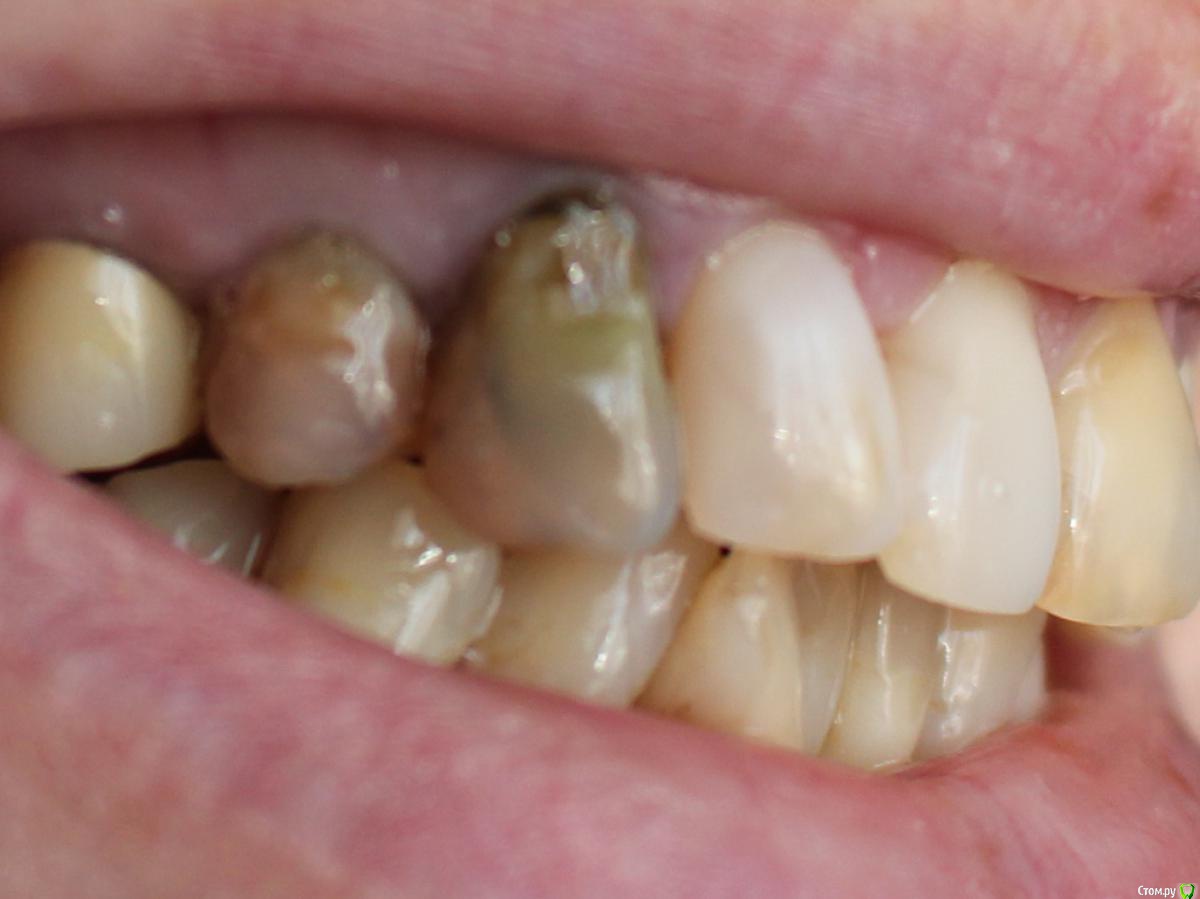

стихия Опубликовано 20 мая, 2018 Поделиться Опубликовано 20 мая, 2018 Здравствуйте, уважаемые стоматологи. Прошу вашего совета вот по такому вопросу. Лет 15 назад у меня были лечены правые верхние 3-й и 4-й зубы. Были запломбированы каналы и в каждый зуб вкручен анкер. Зубы с того времени не беспокоят, стоят надежно. Но есть одна проблема: со временем они стали просто отвратительного серо-желтого цвета и эстетически это выглядит мягко скажем не очень красиво. Несколько раз обращалась к врачам с просьбой что-то сделать с этими зубами, как-то их отбелить, наклеить винир или коронку на крайний случай - все отказывались (( Говорят, выкручивать анкера в моем случае не безопасно, можно разломать корни. Отбеливать тоже отказывались, говорили не поможет, т.к. от самих зубов мало что осталось. И вот недавно, попала я к одному врачу, который сказал, что переделает мне эти зубы. Снимет анкера, поставит стекловолокно, отбелит, нарастит. Я конечно очень обрадовалась и согласилась, но немного побаиваюсь и сомневаюсь: стоит ли их все-таки трогать, может действительно есть большая вероятность, что корни расколются и тогда только удаление... Посмотрите, пожалуйста, мои снимки, и подскажите, есть ли шансы эти зубы переделать и привести в нормальный вид, или лучше не трогать? И если анкера достанут, может лучше сразу коронки одевать? Пы.Сы. каналы в этих зубах вероятнее всего распломбировать не удастся... был аналогичный зуб слева (лечен тем же доктором в то же время) - пришлось удалить из-за кисты, канал не прошли. Ссылка на комментарий